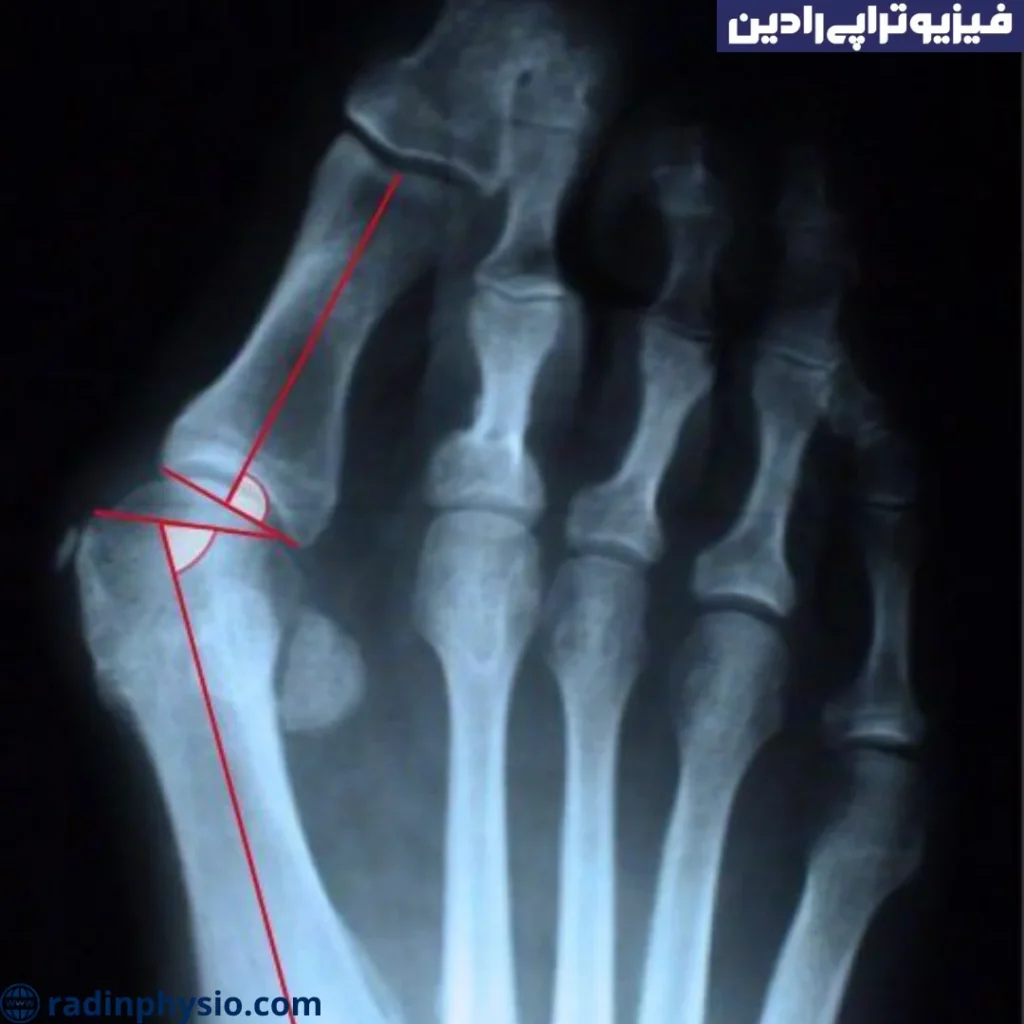

● تصویربرداری: در مواردی که تصویربرداری بیشتر لازم است، پزشک ممکن است از رادیوگرافی (X-ray) استفاده کند تا تصاویری از پا و مفاصل انگشت چنگالی بگیرد. این تصاویر ممکن است نشان دهنده تغییرات استخوانی، مفصلی و ساختاری در پا باشند.